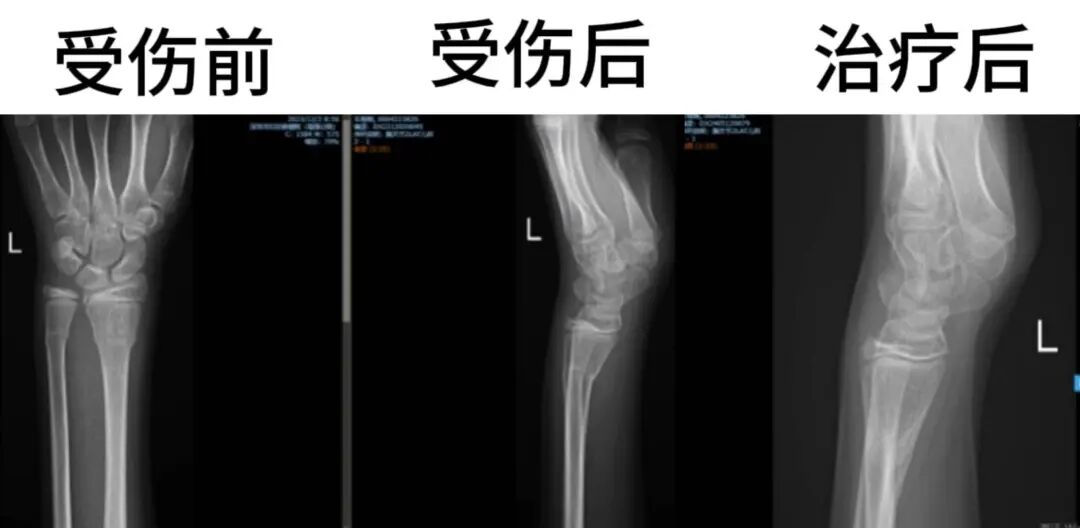

就医后需要拍受伤部位的X片确认是否有骨折,如果是关节内的骨折等情况,必要时还需要做CT进行进一步诊断。

儿童骨折怎么办?

手术“一键”复位

儿童不是成人简单的等比例缩小,所以骨折的治疗方式也和成人有所不同——

●对于稳定的、对位对线良好的四肢骨折,优先考虑通过手法复位+外固定术的保守治疗方案;

●对于复位不稳定、移位严重或者关节内骨折,单纯的手术复位+外固定容易失败,往往需要手术切开复位+内固定治疗。具体治疗方案需要根据受伤部位、严重程度来决定。